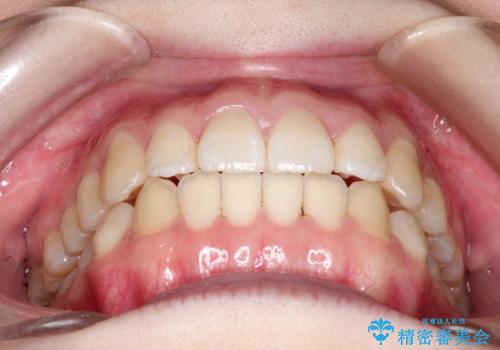

歯列の横幅をひろげるのと、歯と歯の間をわずかに削ることにより、前歯のがたつきと、開咬を改善しました。

- 1年3ヶ月

- 10-30回